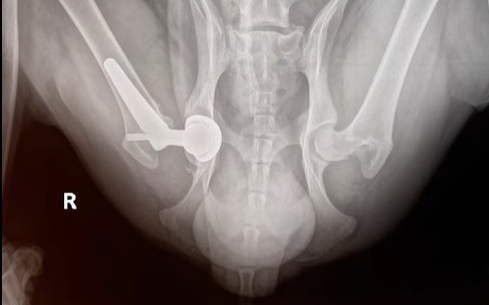

Phẫu thuật THR được xem là một bước đột phá, một thành tựu vĩ đại trong ngành chấn thương chỉnh hình thú y. Trong ca mổ này, phần khớp háng bị tổn thương sẽ được loại bỏ và thay thế hoàn toàn bằng một bộ khớp nhân tạo. Kỹ thuật này rất khó, đòi hỏi đội ngũ chuyên gia phải thực sự giỏi nghề kết hợp cùng trang thiết bị tối tân mới có thể thực hiện thành công.

Để ca mổ diễn ra thành công, các bác sĩ đã tính toán tỉ mỉ một kế hoạch chi tiết. Đội ngũ quyết định sử dụng bộ dụng cụ thay khớp háng THR của BlueSAO – một trong những công nghệ tiên tiến nhất hiện nay, được thiết kế đặc biệt để phục hồi chức năng vận động cho thú cưng. Công nghệ này sở hữu nhiều ưu điểm vượt trội:

Quá trình phẫu thuật diễn ra với độ chính xác cao: Nâu được đặt vào thiết bị chuyên dụng để cố định vùng xương chậu; tiếp đó phần xương và sụn dập nát do tai nạn được cắt bỏ. Bác sĩ tiến hành gắn chỏm xương đùi nhân tạo vào ổ cối nhân tạo, đảm bảo khôi phục lại khả năng vận động linh hoạt cho cơ thể.